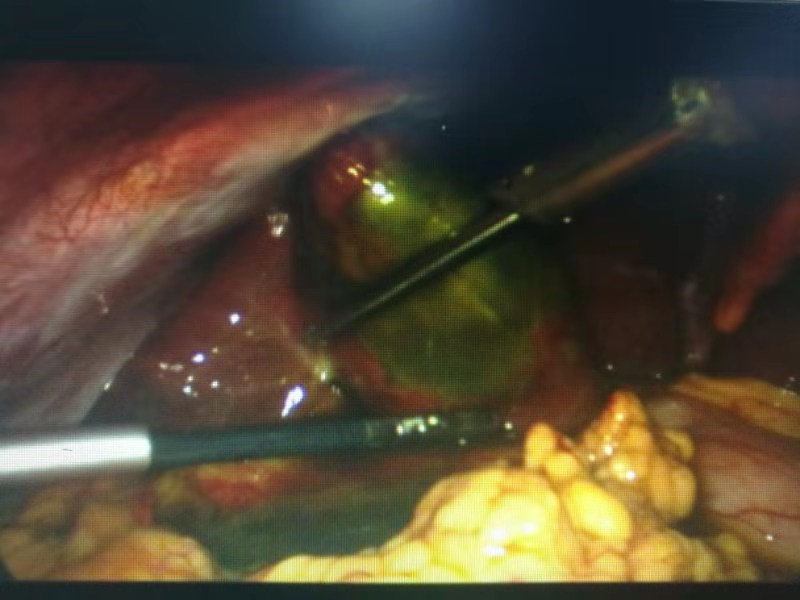

有了周詳?shù)挠?jì)劃,經(jīng)過(guò)充分的術(shù)前準(zhǔn)備,手術(shù)開(kāi)始了。從腹腔鏡下發(fā)現(xiàn),患者膽囊底部壞疽穿孔,膽囊周邊有膽汁滲出。一個(gè)小時(shí)左右,壞疽膽囊和膽結(jié)石被成功取出。

患者術(shù)中照片